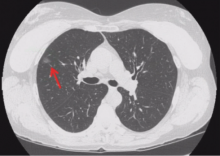

Joseph Shrager of Stanford University School of Medicine in California presents a discussion on the criteria to follow when removing pulmonary nodules and ground glass opacities. He discusses three major questions: when to resect, what type of resection to perform, and what technique to use for single, small ground glass or part-solid/lepidic adenocarcinoma.